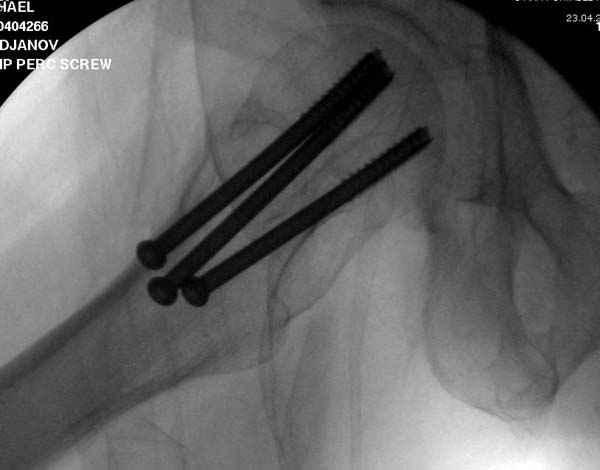

в течение первых 72 часов после перелома, остеосинтез тремя спонгиозными шурупами.

Профилактику дальнейшего раскола неполного перелома шейки провели тремя канюлированными шурупами.

Наверное речь идет насчет parallel guide из набора. Применяем по возможности всегда, но,

как видно на снимке, не всегда получается

паралельно.

Такие несмещенные переломы обычно для молодых резидентов, и бывают технические неточности, но в этом случае посчитали фиксацию адекватной.